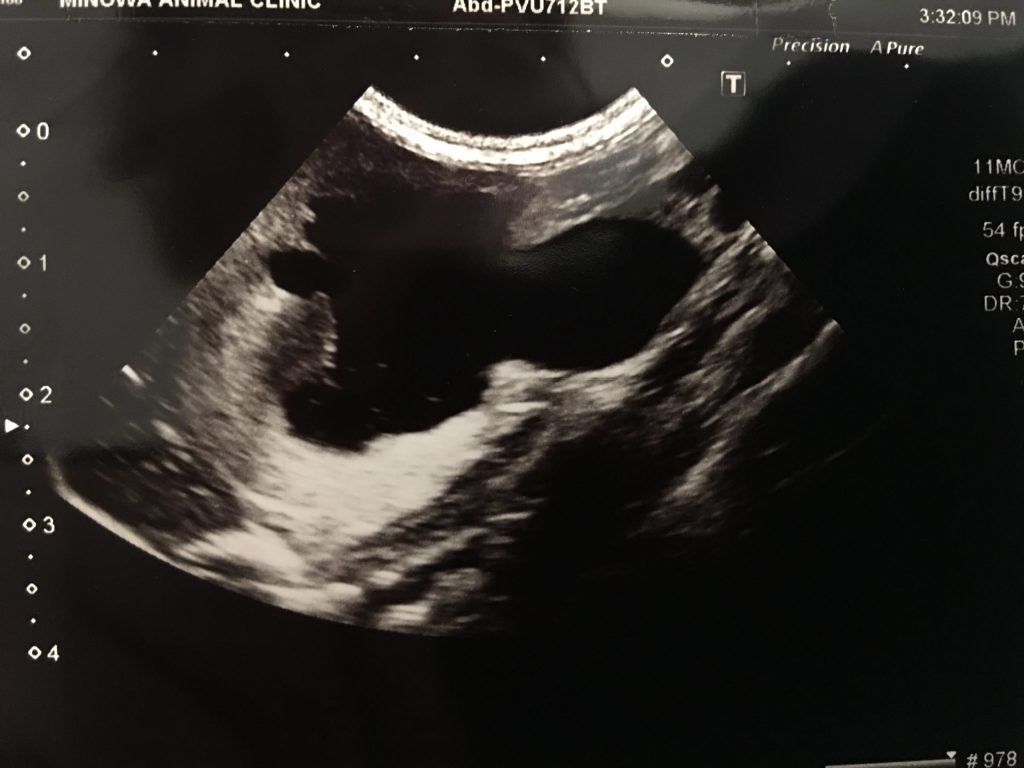

次いで超音波検査およびレントゲン検査を実施したところ、結石により尿管が閉塞し、腎盂の拡張および尿管の拡張が認められました。

今回は尿管の拡張が著しかったため、尿管の切開および縫合を行うことで結石の除去が可能でした。

尿管を切開するとしっかりと結石が詰まっていました。